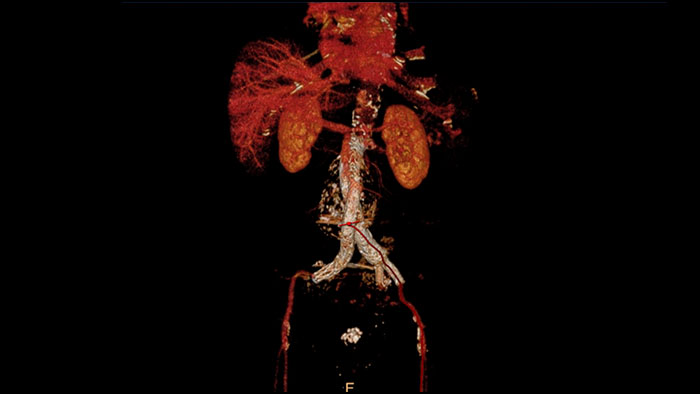

Streamlined modeling workflow

Allows to view volumetric images of anatomical structures, perform segmentation, edit and combine segmented elements (tissues) into a 3D model.

Comprehensive vascular analysis planning

Designed to examine and quantify different types of vascular lesions from CTA and MRA scans. It accommodates different modes of inspection, allows labeling different vascular lesions, and helps navigating through multiple findings. Demonstrated to reduce the post-processing time by 50% when compared to manual Head & Neck CT angiography (CTA) analysis*.